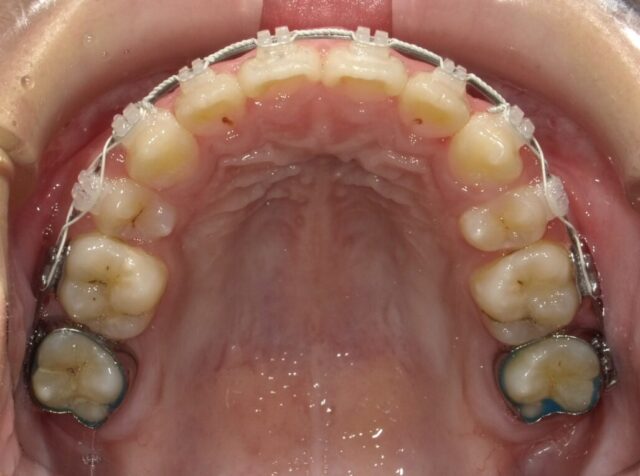

≪上顎咬合面観≫

2023年5月

2023年6月

2023年7月

2023年8月

2023年9月

2023年10月

2023年11月

2023年12月

2024年1月

2024年2月

2024年3月

2024年4月

2024年5月

2024年6月

2024年7月

2024年8月

2024年9月

2024年10月

2024年12月

2025年1月